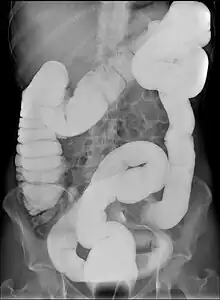

Dolichocôlon

En médecine, un dolichocôlon (mot dérivé du grec ancien dolichos, la course de longue distance et de côlon) est un intestin anormalement long[1]. Il ne faut pas le confondre avec un gros intestin anormalement large, appelé mégacôlon (ou colectasie) .

Le dolichocôlon est souvent une découverte fortuite sur une radiographie abdominale ou lors d'une coloscopie. Ce n'est pas en soi une maladie en tant que telle ne nécessite aucun traitement.